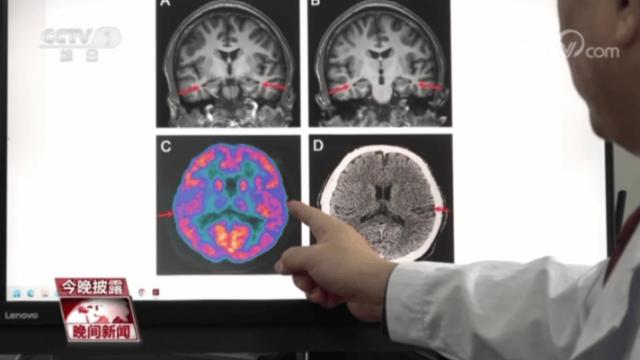

事实上,医生发现近几年因为记忆力下降而来医院看病的年轻人越来越多,在这些病人中,被诊断为阿尔茨海默病的病人也呈现出年轻化的趋势。"首都医科大学宣武医院有一个 19 老阿尔茨海默病患者。”汪子琪说,这个孩子在高中的时候,很难集中注意力,逐渐失去短期记忆,无法回忆前一天发生的事情或者个人物品的存放位置,阅读困难,反应缓慢。

此外,假如有一些精神疾病,比如抑郁症,就会增加。 3% 患病的风险。长时间处于抑郁状态,会损害我们大脑的功能和结构,甚至导致海马体等与大脑和记忆相关的部位萎缩。